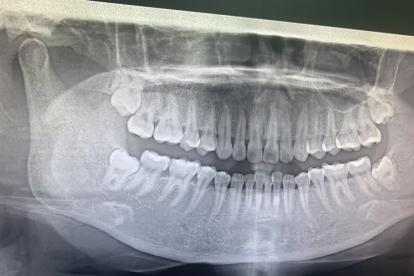

当残留碎片小于3毫米且无感染迹象时,可暂不处理。人体可能通过破骨细胞自然吸收微小残片,期间需每3个月拍摄口腔全景片监测。若出现牙龈包裹形成瘢痕组织,残留物可能被永久固定而不引发症状。建议使用复方氯己定含漱液维持口腔清洁,避免辛辣食物刺激创面。